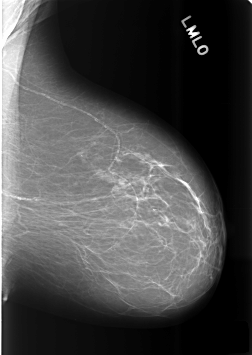

C_0485_1.LEFT_MLO

LEFT_MLO LINES 5680 PIXELS_PER_LINE 4024 BITS_PER_PIXEL 12 RESOLUTION 50 NON_OVERLAY